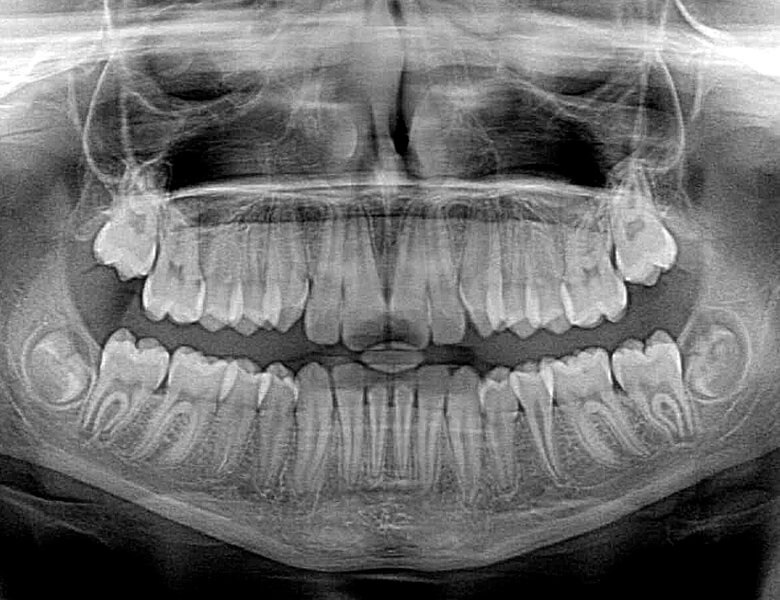

Anhand von Röntgenaufnahmen, Situationsmodellen und Funktionstests bewerten wir Ihre persönliche Ausgangssituation. Mittels digitaler, bildgebender Verfahren können wir die knöchernen Strukturen genau erkennen und die Position Ihrer Implantate exakt planen. Mitunter wird auch bereits der künftige Zahnersatz am Bildschirm dargestellt.